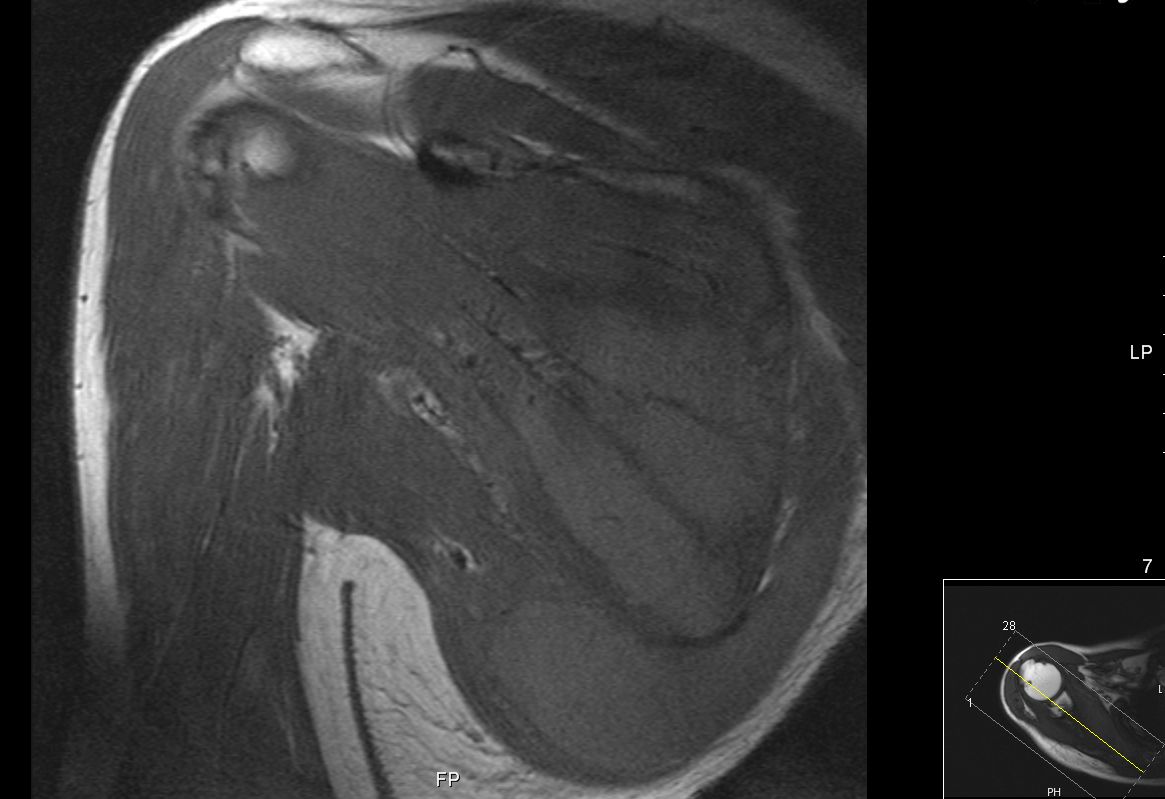

63-jähriger Mann, der vor 5 Jahren eine T - Promyelozyten - Leukämie hatte. Nach ASCT bisher rezidivfrei. Jetzt beschwerden in der rechten Schulter. Das MRT zeigt intramuskuläre Raumforderungen. Die Biopsie ergab Infiltrate der APL.